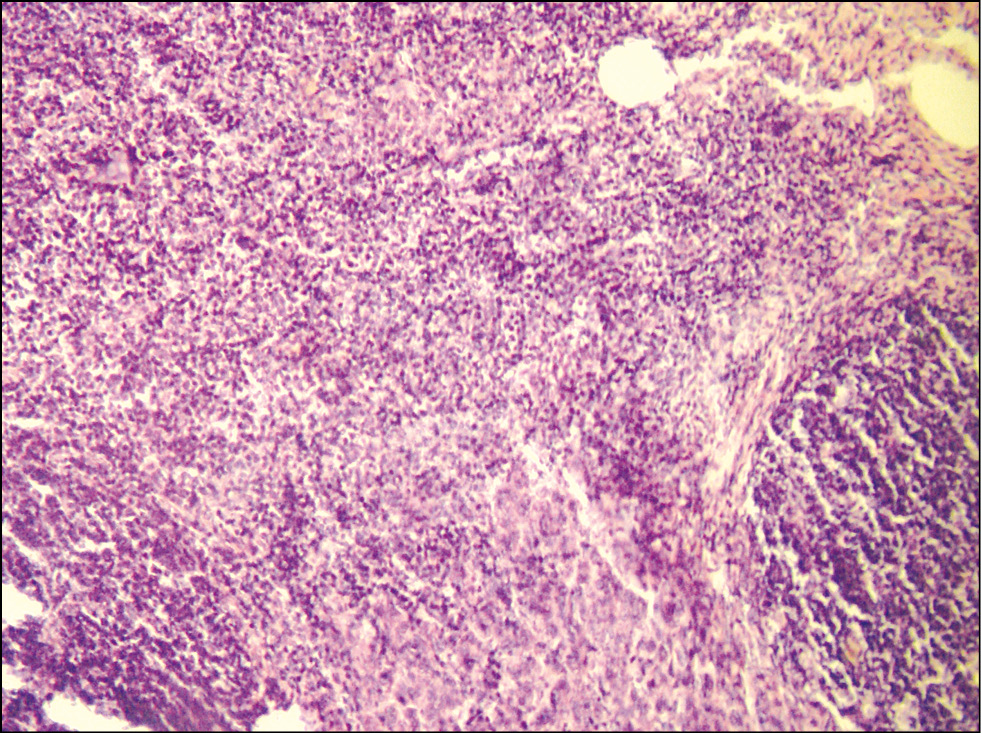

Микропрепарат сердца: полнокровие и отёк интерстиция; фрагментация миоцитов; неравномерная гипертрофия и неравномерное истончение волокон; очаговая стромальная и паренхиматозная жировая дистрофия (рис. 6).

Рис. 6. Микропрепарат сердца. Дистрофия кардиоцитов. Окраска гематоксилином и эозином. Ув. 250 / Fig. 6. Microslide of the heart. Dystrophy of cardiocytes. Staining with hematoxylin and eosin. Magnification 250.